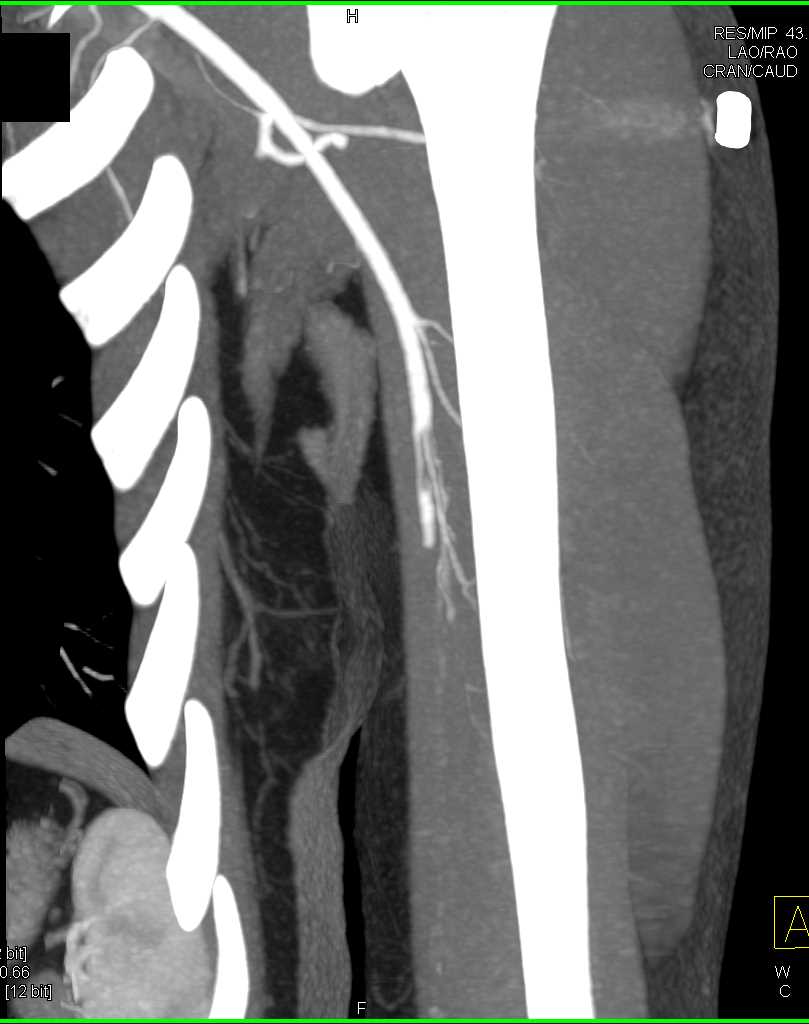

Brachial Artery Occlusion